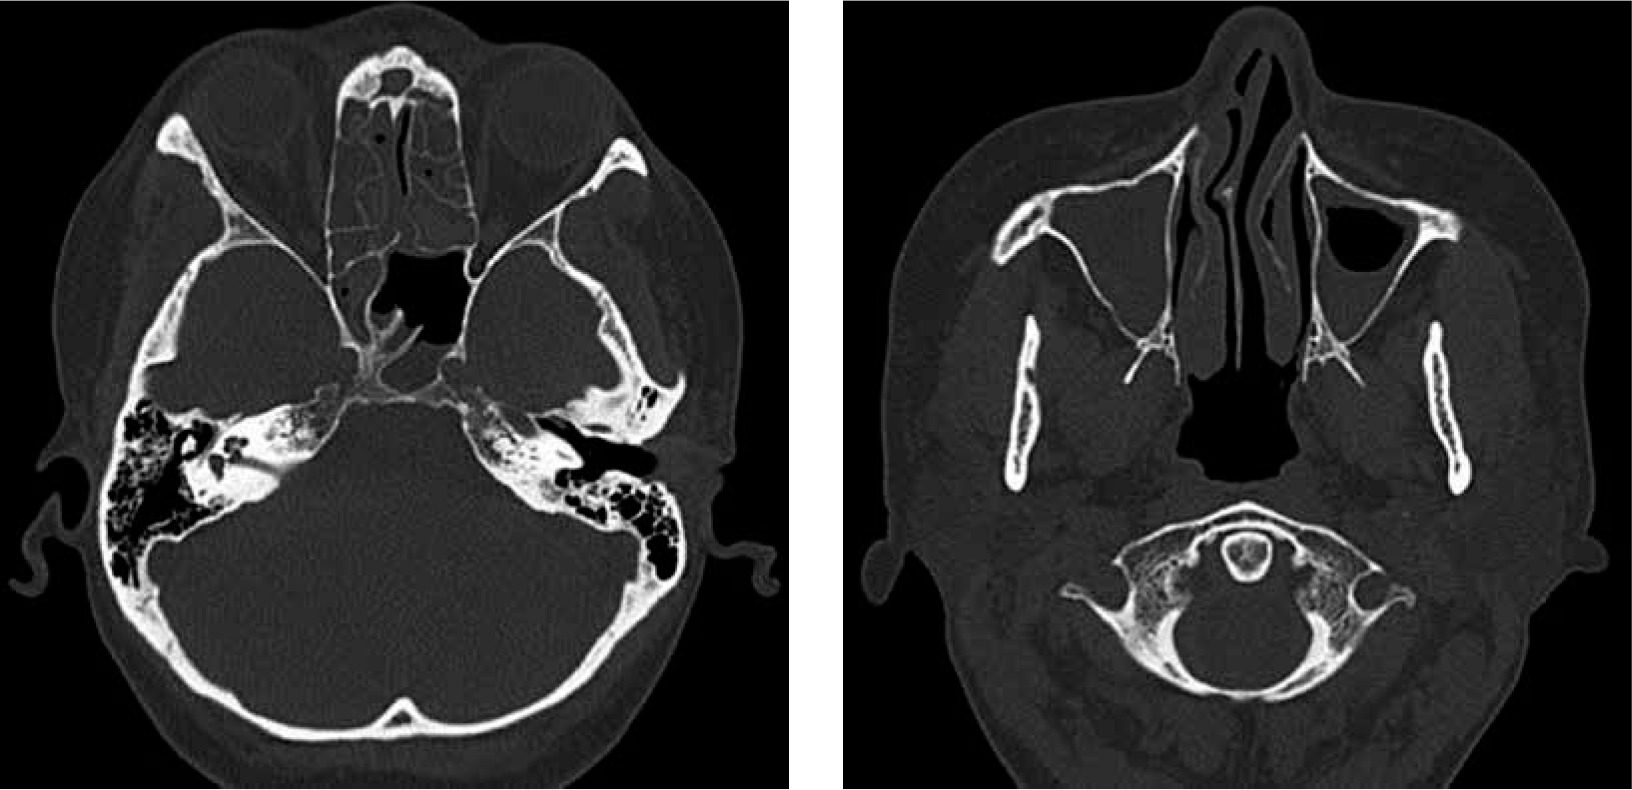

In June 2017, a nonsmoker 48-year-old woman with a history of persistent bronchial asthma and chronic pansinusitis was diagnosed with respiratory failure in the course of hypereosinophilic syndrome. Computed tomography (CT) of the chest showed massive interstitial infiltrates and laboratory tests revealed eosinophilia (8286 cells/µl). Therapy with systemic and inhaled glucocorticoids and inhaled bronchodilators was started, with moderate improvement. Further workup displayed elevated level of eosinophils (8%) in bronchoalveolar lavage (BAL) fluid and negative antinuclear and antineutrophil cytoplasmic antibodies. Previous attempts to taper oral GS led to flare of the disease; therefore the patient had add-on therapy with the humanized anti-IL-5 monoclonal antibody mepolizumab for several months (last dose was given in May 2019). However, instead of the applied treatment and normal level of peripheral eosinophils (< 500 cells/µl) she presented with fluctuating lower respiratory tract symptoms (wheezing, rhonchi, cough, dyspnea), recurrent exacerbations of pansinusitis with persisting hearing impairment (Fig. 1). In July 2019 functional endoscopic sinus surgery was performed, revealing eosinophilic (approx. 10% of the cells) chronic infiltrates of the mucosal stroma.

In December 2019 the patient was admitted to the Department of Rheumatology and Immunology due to exertional dyspnea and cough. Physical examination revealed diffuse expiratory wheezing and prolonged expiration. Initial workup revealed blood eosinophilia (2840 cells/µl) and an elevated level of immunoglobulin E (134 IU/ml, reference range < 100); with normal levels of vitamin B12, tryptase and immunoglobulin G. There were no parasitic eggs or larvae in a stool sample. The patient was negative for FIP1L1-PDGFRA, JAK2 and ETV6-PDGFRB mutations. A bone marrow aspirate revealed an elevated level of eosinophils (< 10% of the cells); no other pathologies were identified. Cytogenetic analysis showed a normal female karyotype. Ground glass opacities on high-resolution CT were described (Fig. 2). Bacterial and fungal cultures of BAL fluid did not yield any organisms. Increased eosinophils in BAL fluid (10%) confirmed HES flare. Therapy with intravenous methylprednisolone (40 mg daily for 5 days, subsequently tapered), combined with inhaled GC and bronchodilators was started. Reduction of methylprednisolone dose less than 32 mg daily led to HES flare.